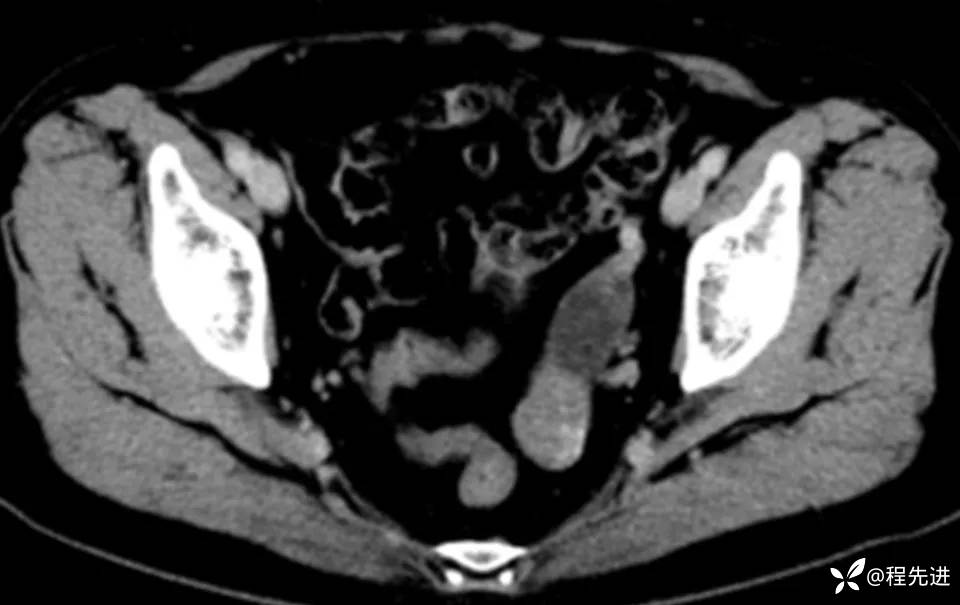

患者性别:女

患者年龄:60岁

简要病史:诊断乙状结肠癌术前常规检查发现

CT平扫+增强: